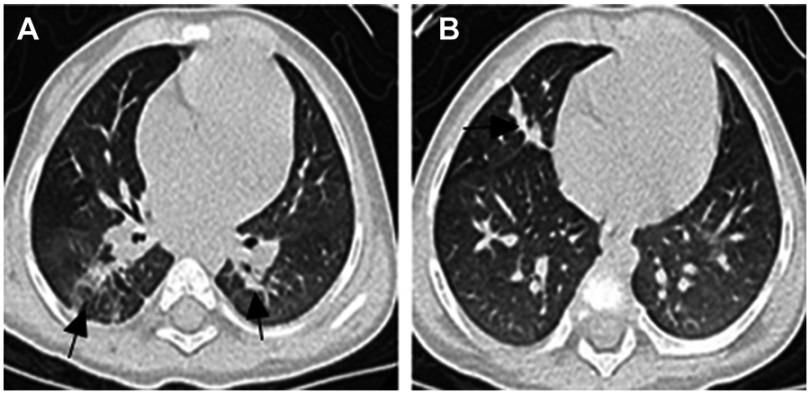

complex (MABC) is an uncommon but increasingly important cause of invasive pulmonary disease, a condition associated with diagnostic and management challenges. MABC has mainly been reported in children with certain medical conditions, such as preexisting structural lung disorders and immunocompromised status. In this article, we describe a rare case of MABC pulmonary disease in an otherwise healthy infant. A 4-month-old female presented with cough and fever for 4 days. Computed tomography showed multiple masses and small nodules across both lungs. Isolated mycobacteria from her bronchoalveolar lavage fluid and gastric aspirate were identified as MABC by using matrix-assisted laser desorption ionization time-of-flight mass spectrometry and subsp. was ultimately identified by DNA sequence analysis. Prolonged treatment with a combination of azithromycin, cefoxitin, and moxifloxacin achieved a successful treatment outcome.

复合非结核分枝杆菌(MABC)是侵袭性肺部疾病的一种罕见但日益重要的病因,这种疾病与诊断和管理挑战相关。MABC主要在患有某些疾病的儿童中报道,如既往存在的结构性肺部疾病和免疫功能低下状态。在本文中,我们描述了一例原本健康的婴儿患MABC肺部疾病的罕见病例。一名4个月大的女性出现咳嗽和发热4天。计算机断层扫描显示双肺有多个肿块和小结节。通过基质辅助激光解吸电离飞行时间质谱法,从她的支气管肺泡灌洗液和胃吸出物中分离出的分枝杆菌被鉴定为MABC,最终通过DNA序列分析鉴定出亚种。阿奇霉素、头孢西丁和莫西沙星联合长期治疗取得了成功的治疗效果。